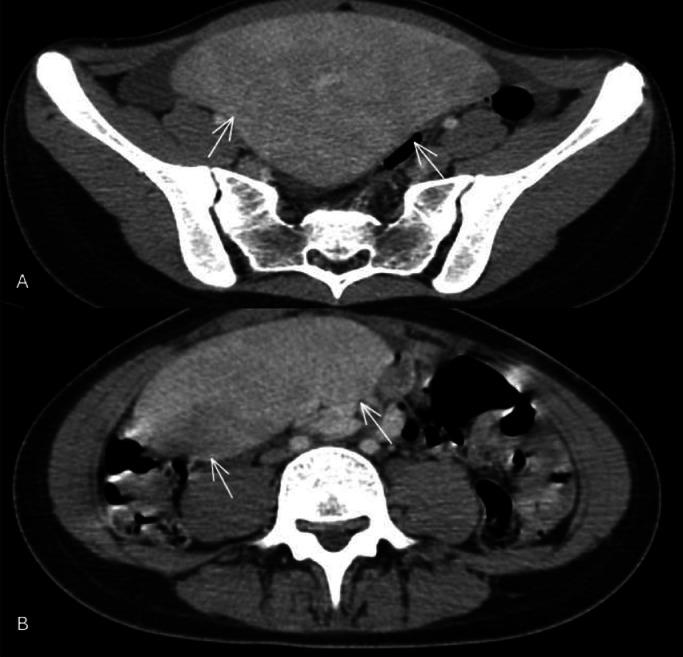

Wandering spleen is a rare condition caused by the absence or laxity of the ligaments that normally hold the spleen in place, resulting in its abnormal mobility within the abdominal or pelvic cavity. We report the case of a 15-year-old girl who presented with acute abdominal pain and nonspecific clinical findings. Abdominal CT revealed an enlarged ectopic spleen in the pelvic region with a long, tortuous vascular pedicle, but no signs of torsion or infarction. This case highlights the variable clinical presentation of wandering spleen, which can range from incidental discovery to acute abdomen, with imaging particularly CT being crucial for diagnosis. In uncomplicated cases, splenopexy is preferred to preserve splenic function, whereas splenectomy is reserved for infarcted or nonviable spleens. The case underscores the importance of considering wandering spleen in adolescents with unexplained abdominal pain and demonstrates how early diagnosis and conservative surgical management can prevent serious complications.

游走脾是一种罕见的病症,由正常情况下固定脾脏的韧带缺失或松弛引起,导致其在腹腔或盆腔内异常移动。我们报告了一例15岁女孩的病例,她表现为急性腹痛和非特异性临床症状。腹部CT显示盆腔区域有一个肿大的异位脾脏,伴有一条长而迂曲的血管蒂,但没有扭转或梗死的迹象。该病例突出了游走脾临床表现的多样性,其范围可从偶然发现到急腹症,影像学检查尤其是CT对诊断至关重要。在无并发症的情况下,首选脾固定术以保留脾脏功能,而脾切除术则适用于梗死或无活力的脾脏。该病例强调了在不明原因腹痛的青少年中考虑游走脾的重要性,并展示了早期诊断和保守手术治疗如何预防严重并发症。